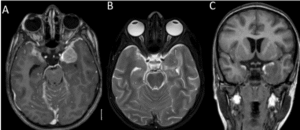

This study involved a retrospective analysis of prospectively collected data from patients diagnosed with sDAVF (type-1) from January 2001 to January 2020. All patients who underwent microsurgical disconnection of an angiographically proven sDAVF during the study period were included in the study. We excluded sDAVF patients treated by endovascular means. We also excluded patients undergoing a revision procedure. Patient consent was obtained for the purpose of the study with due care to maintain his/her privacy. We reviewed outpatient charts, inpatient charts, operation records, magnetic resonance imaging (MRI) scans, and spinal angiograms of these patients during the study period. Age, sex, duration of symptoms, comorbid conditions at the time of admission, sensory/ motor/bladder involvement, pre-intervention Nurick grade (NG),[9] modified Aminoff–Logue’s score (mALS),[10] imaging findings, and post-intervention NG were tabulated and analyzed. The dose of steroid administered, the timing of neurological deterioration, if any, in relation to the administration of steroids and surgery, and the postoperative outcomes in this specific subset of patients were statistically analyzed. The history of any acute neurological worsening before admission was also documented. The MR imaging features during the time of deterioration (wherever available) were also studied. All patients underwent MR imaging of the thoracolumbar (TL) spine with whole spine screening. We diagnosed sDAVF by the presence of T2-weighted hyperintensity within the cord and multiple flow voids in the subarachnoid space. The length of cord edema was measured in each MR image using the number of vertebral segments involved. Thin T2W coronal cuts were used to further identify the level of fistula, once the flow voids were identified on the sagittal images. All patients also underwent preoperative spinal angiograms [Figure 1] to confirm the diagnosis and ascertain the level of the sDAVF. The presence and location of the sDAVF were confirmed and agreed upon by all the authors. When the patients developed any acute preoperative neurological worsening after admission, an MRI of the spine was obtained whenever feasible. This imaging was examined for any new or increased T2W cord changes or bleeds

Seven of the 62 sDAVF patients (11.3%) who underwent microsurgical excision experienced an acute neurological deterioration upon admission to our hospital [Figure 2], while 55 had no neurological worsening. All seven patients were male, and their ages varied from 35 to 73 years, with a mean age of 54.7 years ± 12.5 [Table 1]. The average length of symptoms before surgery was 15.7 months ± 29.1 (median: 12 months, range: 3–60 months). We observed that progressive myelopathy, the most common clinical syndrome at the time of presentation, was present in 93.4% of our patients. In total, 86% of our patients had bladder involvement. Furthermore,